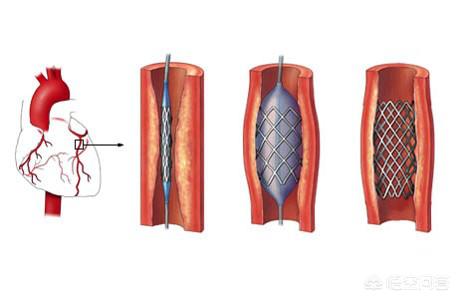

ステップ1、パンク。末梢動脈を見つけ、この動脈から穿刺を行うが、最も一般的な選択は、手の付け根か太ももの末梢動脈を選択することである。

ステップ2、チューブの挿入。その末梢血管開口部からシースを挿入し、適切なサイズのシースを選択してガイドワイヤーを進め、冠動脈開口部付近の心臓までゆっくりと送り込む。

ステップ3:軌道を確立する。最初のガイドワイヤーは冠動脈より太いので、この時は細いガイドワイヤーを選んで冠動脈病変の遠位部を通過させ、まずバルーンで拡張しなければならない。

ステップ4:ステントを留置する。バルーンの拡張が完了したら、このガイドワイヤーに従ってステントを留置する。

これが心臓ステント手術の大まかな流れだ。 経験を積んだ。熟練した医師は、この手術を30分以上かけて行う!そのため、心臓ステント手術を専門とする医師にとっては、そうである。大きな作戦ではない。。